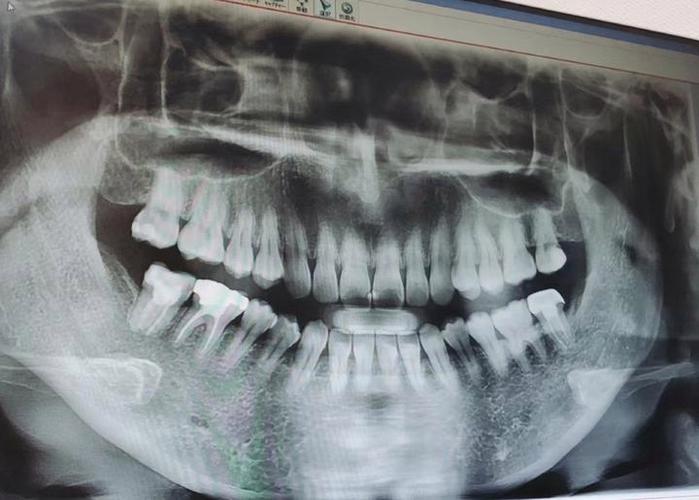

正畸前,医生需通过临床检查(如牙周探诊、牙齿松动度评估)和影像学检查(根尖片、曲面断层片、CBCT)明确牙根短的具体程度、范围及牙周健康状况,CBCT可三维重建牙根形态,精确测量牙根长度、牙槽骨高度及厚度,判断是否存在根尖周病变、骨开裂或骨开窗等风险,这是评估正畸可行性的基础。